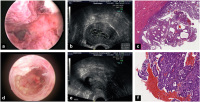

Abbildung 2a-f: Pathologische Veränderungen des Uterus, die für Blutungsstörungen verantwortlich sein können (links: hysteroskopische Bilder; Mitte: Ultraschallbilder; rechts: Histologie. Die Bilder sind nur beispielhaft und identisch mit dem Fall links). Alle Abbildungen von den Ko-Autoren zur Verfügung gestellt. Reihe 1: (a): Hyperplastisches Endometrium (Histologie: adenomatöse Hyperplasie) im hysteroskopischen Bild: Unregelmäßig konfigurierte, hochaufgebaute Schleimhautareale im Bereich des Uterusfundus, die beide Tubenosteen bedecken (S. Rimbach); (b): Glandulär-zystische Hyperplasie im Ultraschall: Noch gut begrenztes, jedoch hoch aufgebautes und zystisch verändertes Endometrium (M. Elsässer); (c) Glandulär-zystische Hyperplasie (histologischer Befund): Einfache Endometriumhyperplasie mit Ausbildung wulstiger, polypöser Epithelabfaltung und unregelmäßig proliferierten, glandulär-zystischen Endometriumdrüsen (ohne Atypien) (P. Sinn). Reihe 2: (d): Endometriumkarzinom im hysteroskopischen Bild: Unregelmäßig konfigurierte, hochaufgebaute Endometriumschleimhaut im Uterusfundusbereich mit z. T. soliden Arealen (S. Rimbach); (e): Korpuskarzinom im Ultraschall: Typisches Bild eines Endometriumkarzinoms, welches sich durch intrakavitäre Flüssigkeit, solide-papilläre intrakavitäre Strukturen und schlechte Abgrenzbarkeit (hier zur Vorderwand) zeigt (M. Elsässer); (f): Korpuskarzinom (histologischer Befund): Oberflächliche Formationen eines gut differenzierten, endometrioiden Adenokarzinoms des Corpus uteri (P. Sinn).